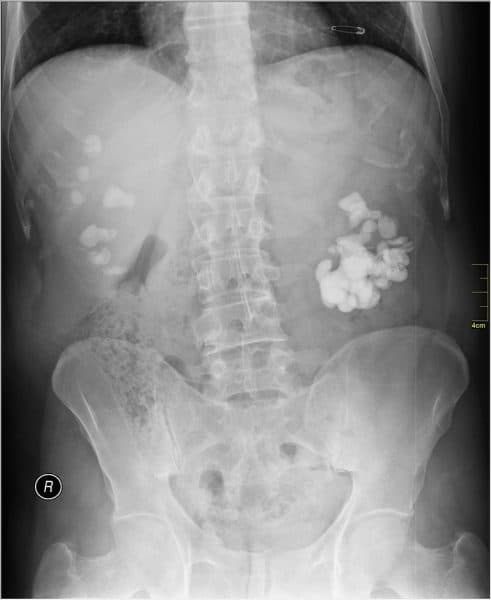

– Bệnh nhân sẽ được chụp phim ở hệ tiết niệu. Kết quả phim chụp giúp phát hiện ra sỏi, vị trí sỏi, các dấu hiệu kích thích đường tiêu hóa như bóng hơi trong dạ dày hoặc đường ruột.

– Tiến hành siêu âm ổ bụng cho phép phát hiện sỏi cản quang và không cản quang cũng như hình ảnh giãn đài bể thận và kích thước sỏi .

– Chụp cắt lớp dựng hình hệ tiết niệu để chẩn đoán chính xác kích thước, vị trí sỏi, đánh giá chức năng thận, mức độ ứ nước thận và đường bài xuất.

– Phân biệt trong phòng cấp cứu để loại trừ viêm ruột thừa, viêm túi mật cấp, viêm tụy cấp, viêm phần phụ. Trong các trường hợp khác, cần loại trừ u đài bể thận, u niệu quản, các sỏi túi mật, sỏi tụy, các hạch vôi hóa vùng khung xương chậu.